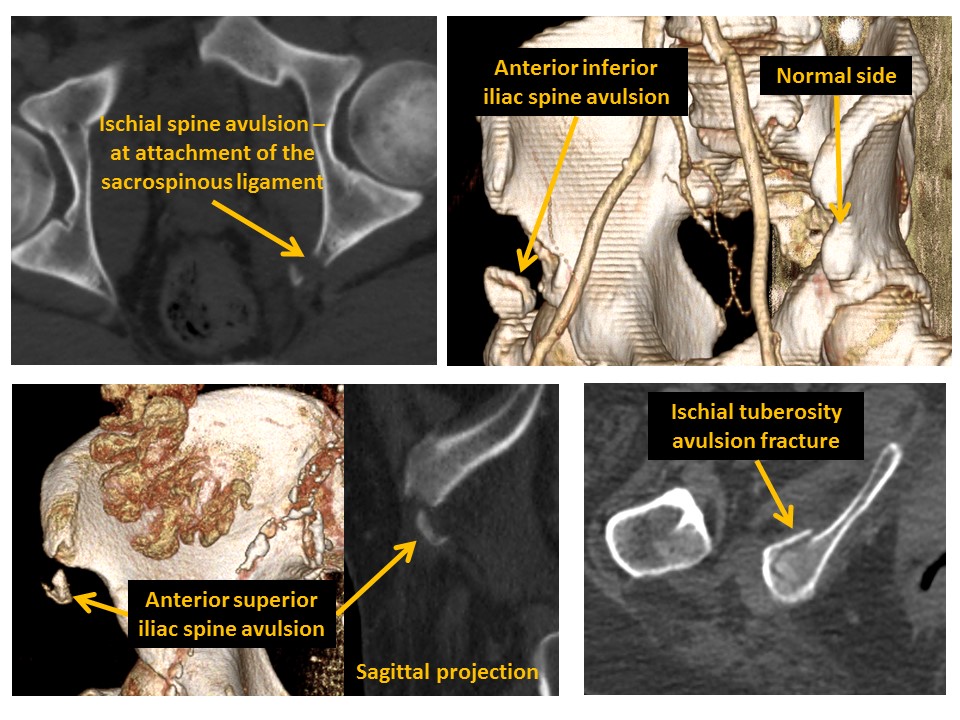

INNOMINATE BONES

There are cortical disruptions or displaced fractures. [Yes/No]

Avulsion fractures are present. [Yes/No]